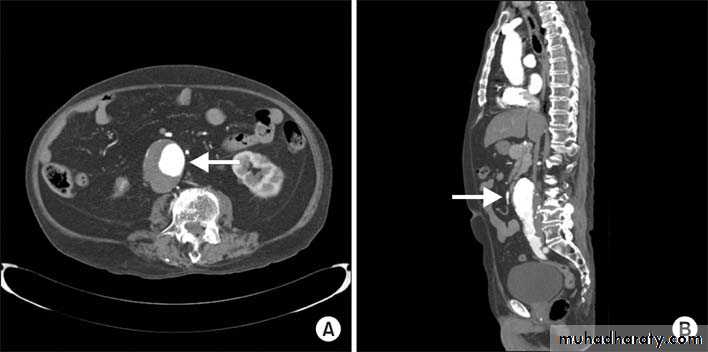

CT & CT angio of abdominal aortic aneurysm

Ruptured abdominal aortic aneurysm